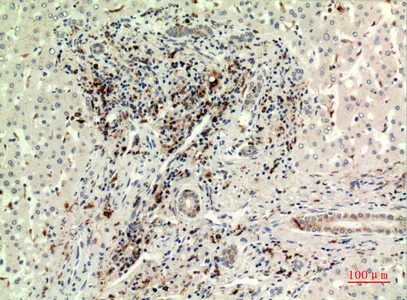

c-Fms Rabbit Polyclonal Antibody

Cat: APRab08705